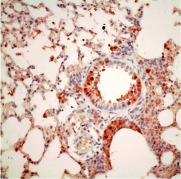

In a recent study reported in the Nature Communications, a research team led by Dr. Honglin Chen, Associate Professor, and Professor Kwok-yung Yuen, Henry Fok Professor in Infectious Diseases, Chair Professor of Infectious Diseases from the Department of Microbiology, Li Ka Shing Faculty of Medicine, and State Key Laboratory for Emerging Infectious Diseases, the University of Hong Kong, found that avian influenza A H5N1 and H7N9, and seasonal H3N2 viruses may gain the ability to replicate in mammal and human cells through various adaptation changes in the viral replication enzyme complex called the PB2 subunit. They found that H7N9 avian influenza A virus is able to utilize multiple adaptive strategies to replicate in human cells, which may explain why H7N9 is distinct in causing human infections; This study identified a novel adaption marker, PB2-526R among some H7N9 viruses and almost exclusively among all H5N1 human cases from Indonesia. It has been a puzzle why there is no known PB2 adaptation marker in the H5N1 virus from Indonesia human cases and the finding from HKU nicely explained how this Indonesian subclade of avian H5N1 virus may have adapted for human infections. This study also found PB2-526R is able to enhance replication and pathogenicity of other types of PB2 adaptations, such as previously known PB2-627K, in H7N9 and H3N2 viruses. Since the human pandemic H3N2 virus emerged in 1968, it has gained an additional PB2-526R adaptation marker since 1970s and the PB2-526R-627K virus replicates better than the solely PB2-627K virus. It is likely that the impression of more severe disease burden caused by H3N2 than that of H1N1 may be partly attributed to the better replication ability of PB2-526R-627K virus. These findings by HKU provided new insight for the understanding of cross species transmission and replication in human cells by avian influenza viruses. The study provides a new genetic marker for the surveillance of avian influenza A virus with potential for human infection.